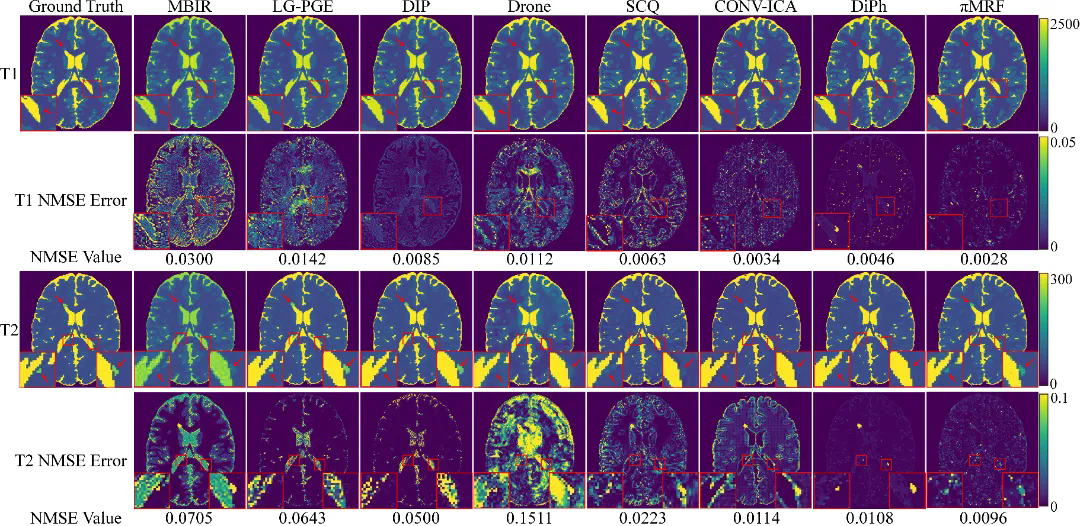

在数字仿真、水模仿体以及在体人脑实验中,πMRF在极端欠采样条件下均表现出更高的定量准确性与空间一致性,能够稳定恢复T1、T2和PD参数分布,并在组织边界及病灶区域保持更可靠的细节表达,整体性能显著优于现有对比方法。上述结果表明,该研究有效缓解了 MRF 在极端欠采样条件下面临的不适定逆问题,展示了“物理模型与陆续在神经表示深度融合”在复杂医学成像反演任务中的应用潜力。

图3:数字仿真实验结果